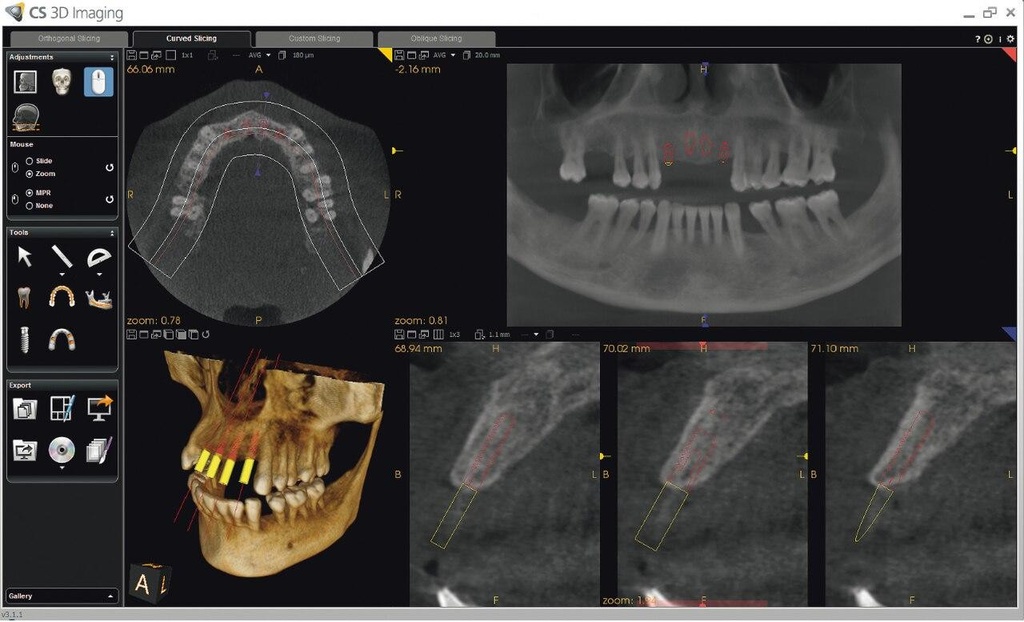

Introducing the CS 9300 Premium Panoramic, Cephalometric, and Cone Beam System from Carestream Dental – your ultimate solution for top-quality dental imaging. This state-of-the-art machine offers both 2D panoramic and cephalometric dental X-rays, as well as adjustable 3D cone beam images in up to seven different field of view sizes, extending up to 17x13.5 cm. This comprehensive range of imaging capabilities makes it a versatile tool, perfect for supporting a wide array of dental, surgical, or orthodontic examinations.

With the CS 9300 Premium, you can expect unparalleled image clarity and precision, allowing you to confidently diagnose and plan treatments with ease. Whether you're performing routine dental check-ups, complex surgical procedures, or orthodontic assessments, this system ensures outstanding results.

The CS 9300 is a multimodality imaging system that offers a wide range of 2D and 3D imaging options.

The CS 9300's 2D panoramic x-ray imaging capabilities are powered by variable focal trough technology, which provides optimal clarity for every image. The system's 3D imaging capabilities are based on cone beam technology, which delivers high-resolution images with a low radiation dose.

The CS 9300 is a versatile imaging system that can be used for a wide range of dental applications, including:

- Orthodontics

- Endodontics

- Implantology

- Oral and maxillofacial surgery

- TMJ disorders

The system's multimodality capabilities make it an ideal choice for dental practices that need a comprehensive imaging solution.